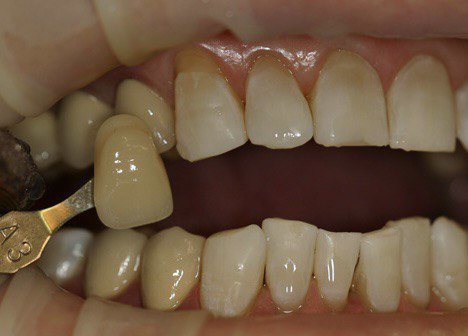

Пациент 51 года обратился с жалобой на тёмные зубы.

Проведено отбеливание зубов с применением диодного лазера.

До процедуры цвет зубов А3 по шкале VITA, после процедуры цвет зубов В1 по шкале VITA.